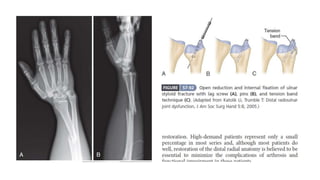

3. Distal radio ulnar joint is immobile:

b. Open reduction is needed to remove the interposed soft

tissue.

c. TFCC and dorsal capsule is repaired.

d. Immobilization is supination and k wire if needed for 6 weeks.